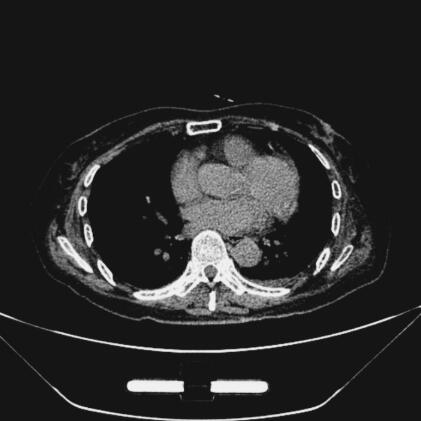

26日8时30分,复查B型脑钠肽2755pg/ml、心肌钙蛋白-I 8.92μg/L,给予静脉泵入新活素(冻干重组人脑利钠肽),同时限制液体输入,加强利尿,使出入量呈负平衡,在500ml左右,并控制血压,使收缩压<130mmHg,减轻心脏前后负荷,经采取上述治疗措施后,动态监测心肌钙蛋白-I、B型脑钠肽,指标逐日降低(图3、图4),症状明显改善。入院时应用美罗培南抗感染治疗,2天后出现发热,体温最高达38.2℃,WBC最高达39.52×109/L,N 95%,CRP最高达257mg/L,改用莫西沙星注射液400mg,每日1次,治疗第2天未再发热,WBC、CRP逐日下降至正常(图5),胸部CT示双肺炎症明显吸收(图6、图7),感染得到有效控制。

图7 治疗后胸部CT示双肺炎症明显吸收(纵隔窗)